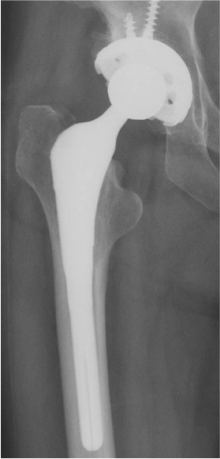

人工関節置換術(THA)

特に関節が強く破壊された状態を「末期」といい、通常は人工関節しか方法はありません。人工股関節に置換することによって、関節の痛みや歩行障害などが改善すると思われます。手術後は、リハビリテーションプログラムにそってリハビリを行い、通常の手術では術翌日から歩行を開始し、入院期間は2週間の予定です。

手術後の合併症として感染、脱臼、血栓症(下肢静脈血栓症、肺血栓症)、人工股関節のゆるみなどがありますが、種々の対策を講じて、その発生の予防に努力しています。